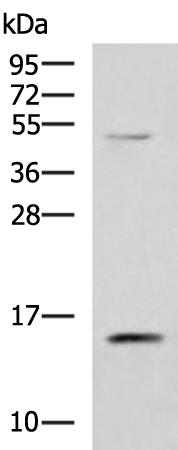

分类: 科研抗体货号: P10236别名: TIM16; MAGMAS; SMDMDM; TIMM16; CGI-136应用: WB,IHC反应种属: Human, Mouse